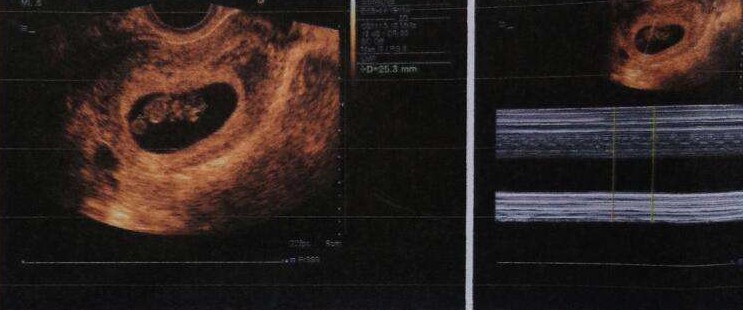

之后的每一天我都能看见试纸加深,一直到14天去抽血,抽血结果HCG六百多。 不过我在移植的第12天的时候开始见红,又开始各种担心和不知所措,怕好不容易的宝贝离开我们。之后就一直开始不停的流血,药渣里面全部是黑褐色的。但是还好B超和血值都是正常的,现在B超已经可以听到宝宝的心跳声了,希望接下来宝宝好好的。

终于等到第14天了,去医院验血,报告中午出来的,没想到成功怀孕了,医生说我才两个胚胎,没想到竟然一次成功,现在看来血值不错,真的很棒! 后面的一报和二报都是抽血,三报做的第一次B超,确认宫内单胎,移植的两个冻囊胚着床了一个。虽然很可惜,但是我觉得能完成我当妈妈的心愿,我已经很感恩了,不敢祈求太多,让我的宝宝健康平安就是我人生最好的礼物了!

第十天一早去医院抽血,HCG108,真的很开心,8月7日去医院做了一超,已经可以看到卵黄囊,胎心和胎芽了,真的太激动了。这次移植我特意做了以下准备,因此这次成功了就把自己的方法推荐给大家,大家可以根据自己情况参考。1、喝鸡汤、吃海参、吃阿胶坚持一个月;鸡我买的土鸡,海参随便,阿胶我是自己买了东阿阿胶自己回家做的,外面卖的100多一斤的阿胶糕我可不敢买,假的太多,里面有没有阿胶都不知道。2、每天走路1万步以上坚持了半个多月;走路是为了让身体底子更好一次,我太懒,不愿意做别的运动,走路还能坚持,希望运动的可以跑步,据说可以加快子宫血流。3.美国保健品---子宫康,这个是我的生殖管家给我推荐的,说是可以帮助增加内膜血流,帮涨内膜,增加宫颈粘液帮助着床,想着买来试试,这家伙确实很活血,移植前我的内膜是10A。除了上面的辅助治疗外,主要成功可能还在我的心情,前面2次在床上躺着一点不动,天天在家脑子里就只剩下成不成的问题了,这样真的不好,所以这次我该干啥干啥,有时候我都忘了自己移植了,哈哈,但我没有拎重东西,没有快走,走路很慢,凉的寒的活血的等等一切不利的都不吃,虽然心情放松了,但是行动上不能放松,一定要注意注意再注意。最后也祝大家早日怀孕!!!